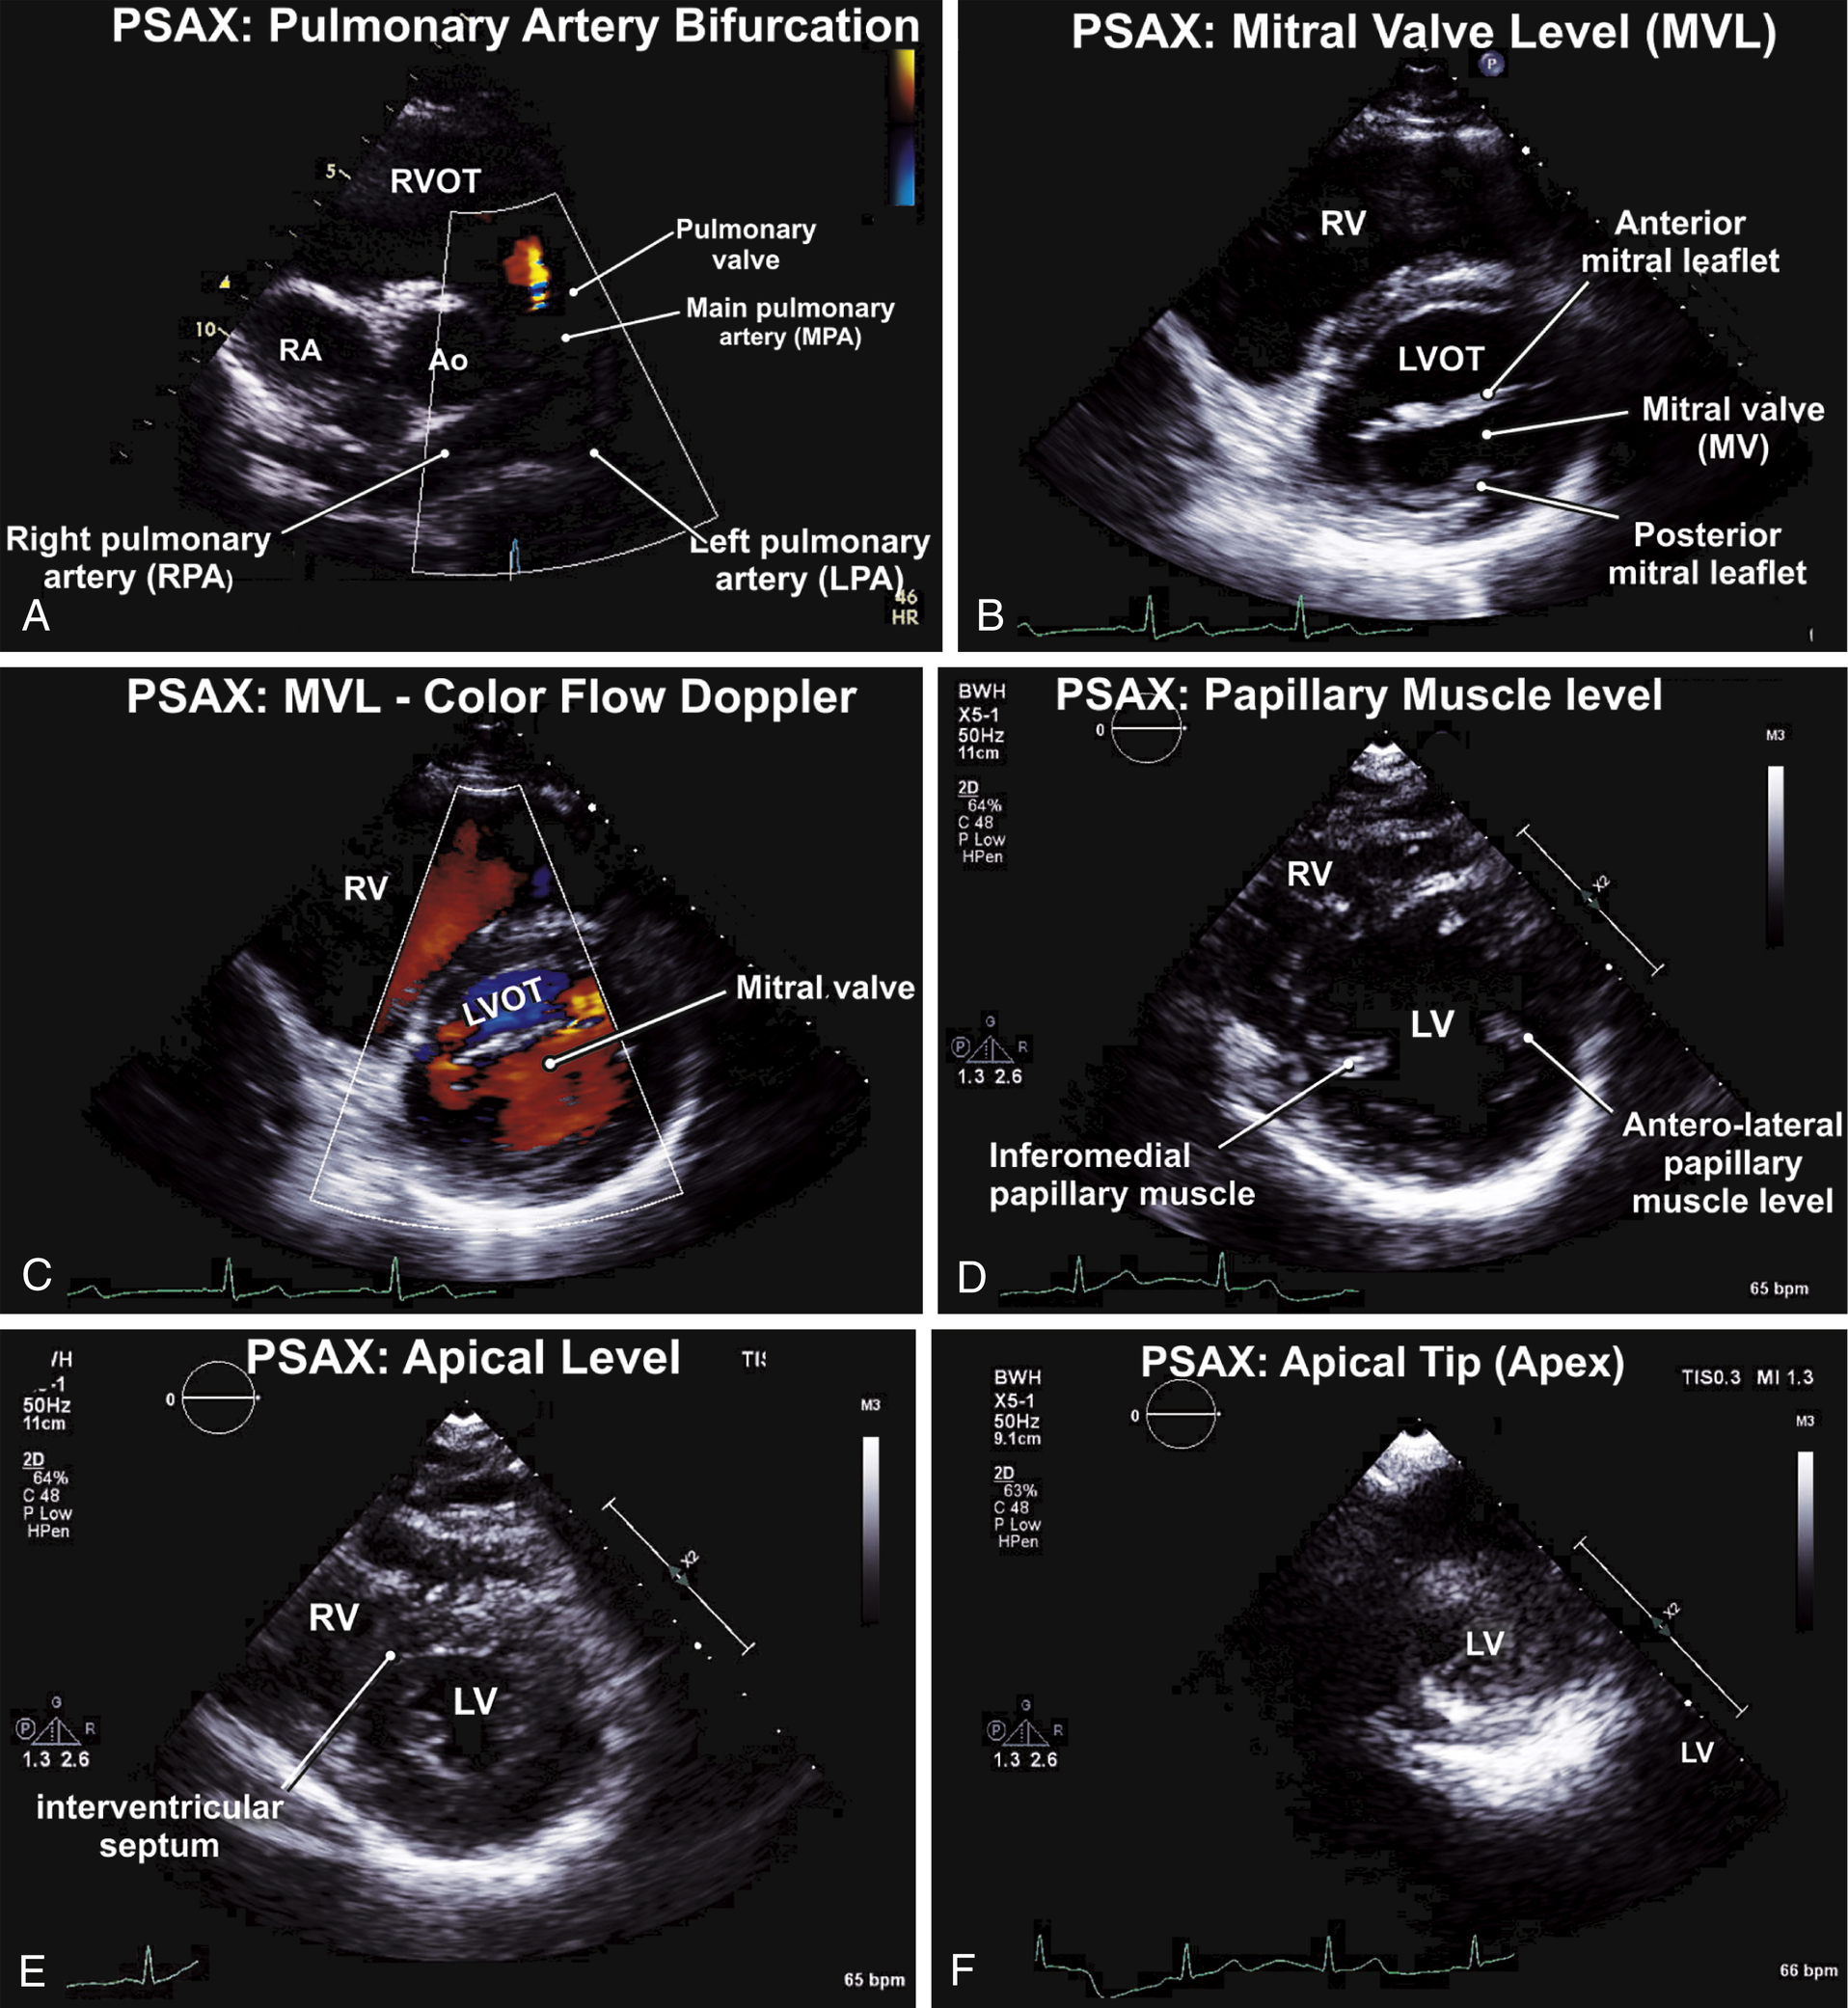

| P | SAX | PA bifurcation: main PA, PV, RPA, LPA, coronary arteries |

| P | SAX | Mitral valve level: MV, basal LV walls, LVOT, IAS |

| P | SAX | Papillary muscle level: LV walls, papillary muscles; IAS |

| P | SAX | Apical level: apical LV walls; LV apex (apical tip) |

TABLE 9.3

Parasternal Short-Axis Views: Normal Examination (see Figs. 9.3 and 9.4)

| PSAX: pulmonary artery bifurcation (PAB) | 2D image of PAB | CFD for PR and PDA | PW-CW of PV |

| PSAX: Mitral valve level (MVL) | 2D image at the MV and basal LV walls | CFD to MV | — |

| PSAX: papillary muscle level (PML) | 2D image at PML, mild LV walls | — | — |

| PSAX: apical level | 2D image at LV apical walls and LV apical segment | — | — |